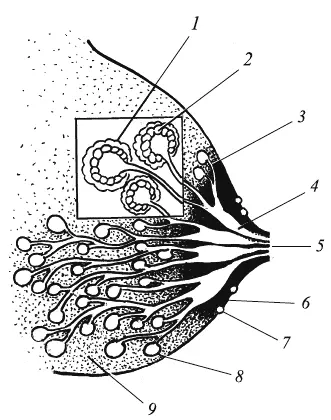

● Что нужно знать о строении молочной железы?

Молочная железа состоит из 15–25 разветвленных долек железистой ткани. На конце каждой ветви гроздьями собраны железистые клетки – альвеолы. Они секретируют молоко. Вокруг альвеол расположены мышечные клетки, при сокращении которых выделяется молоко. По млечным протокам оно поступает к хранилищу молока – млечным синусам. Проекция синусов находится под ареолой. Выделение молока наблюдается только при сдавливании млечных синусов. Около 10–20 выводных млечных протоков открываются на вершине соска. Ареола и сосок снабжены большим количеством нервных рецепторов, содержат особые железы, которые в период лактации выделяют смазку. Секрет смазки защищает кожу соска и ареолы от повреждения, обладает бактерицидным действием, дает специфический запах. Учитывая строение молочной железы (рис. 1), нужно соблюдать следующие рекомендации по кормлению грудью.

Рис. 1. Строение молочной железы:

1 — мышечные клетки; 2 — клетки, секретирующие молоко; 3 — протоки; 4 — млечные синусы; 5 — сосок; 6 — ареола; 7 – железы Монтгомери; 8 — альвеолы; 9 — опорная и жировая ткань